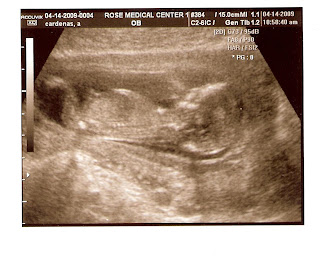

This is the only position that seems to be comfortable and for those of you who are curious my belly tattoo is getting bigger daily. Overall I feel really great and Russell is taking amazing care of me and getting the house ready for baby times ahead. We are reading all the books and talking about all the decisions. We are preparing for a home birth and we are really excited. We are doing so many things to prepare, so if you have any advice for preparations....Let us know.